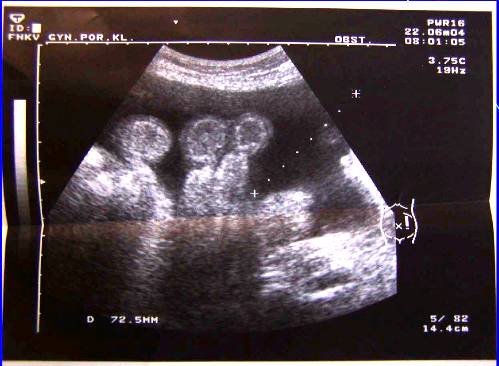

3.Duplicita (pac.M.B.-tu markery, laparotomia, radikální operace pro Ca ovarii, peroperační biopsie)

Duplicita (pac.M.B.-tu markery, laparotomia, radikální operace pro Ca ovarii, peroperační biopsie)

Duplicita(pac.M.B.-tu markery, laparotomia, radikální operace pro Ca ovarii, peroperační biopsie)

Duplicita (pac.M.B -laparotomia, radikální operace pro Ca ovarii, peroperační biopsie)